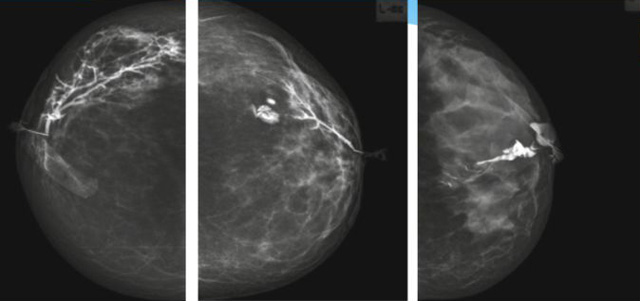

乳腺导管内乳头状瘤分为以下两个,位于乳晕区大导管的中央型乳头状瘤,起源于末梢导管小叶单位的外周型乳头状瘤。外周型乳头状瘤常常没有明显的的临床表现,常因X线或乳腺超声设备检查发现。重点要关注的是中央型乳头状瘤,发生于任何年龄的女性,以40~50岁者居多。它表现为:单侧乳头溢液,特别是血性溢液少数病人可在乳晕区触及肿块。从病理学上面讲表现为导管上皮和间质增生形成有纤维脉管束的乳头状结构。这是它一个病理学上的表现。它的超声表现为:病变导管囊状扩张呈无回声,内可见乳头状低回声或中等回声。乳晕处的导管扩张,管腔内可见边界清楚的,低回声实性结节。外周型导管内乳头状瘤可,表现扩张为为低回声的实性结节,CDFI:部分肿瘤可显示为轴心性的看到血流信号。乳腺增生症:可见导管扩张,内无乳头状实性回声,导管内乳头状癌:囊内乳头状癌病变较大,不规则,厚基底,血流丰富。以囊性为主的混合回声,形态不规则,内见实性低回声实性低回声可见少量血流,病理为囊内乳头状癌。